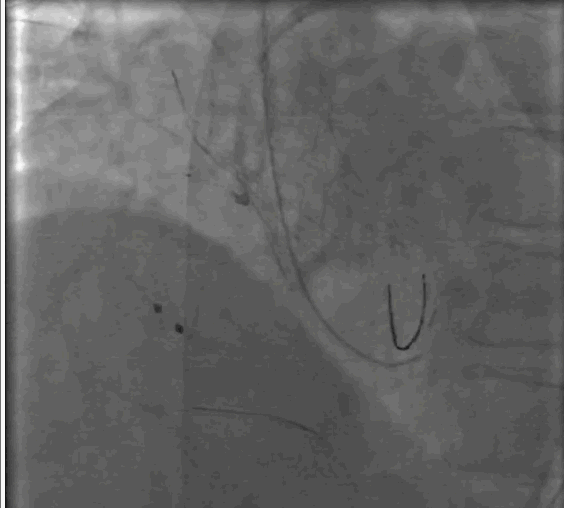

按照预先制定手术策略,首先,周玉杰教授内科团队首先进行左右冠脉保护,然后进行超硬导丝跨瓣进,23mm快速起搏预扩,左右冠脉均无显影,证实冠脉预先评估无误,选择右冠脉居中体位释放,利用瓣膜底部与无冠猪尾导管定位,快速起搏开始释放,释放至限位,由于是可回收系统进行多次反复观察评估冠脉情况,释放位置稳定较好,确认冠脉无风险完全释放瓣膜,撤出体外。